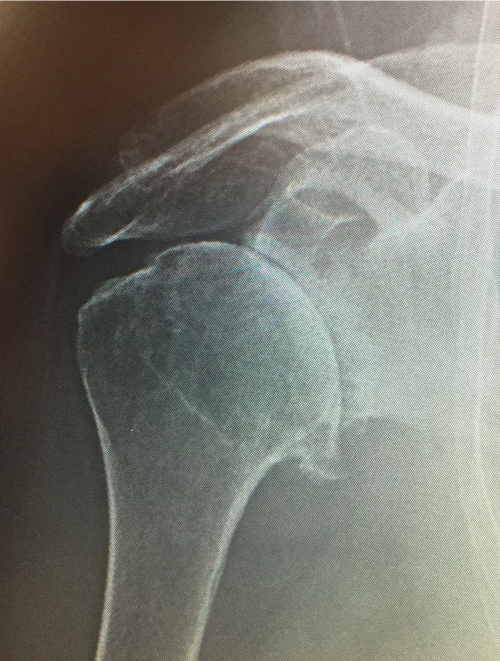

Anatomic Shoulder Replacement